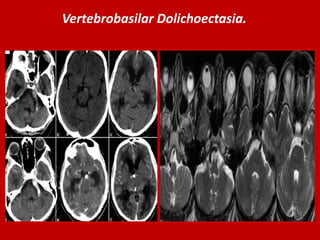

Vertebrobasilar Dolichoectasia.